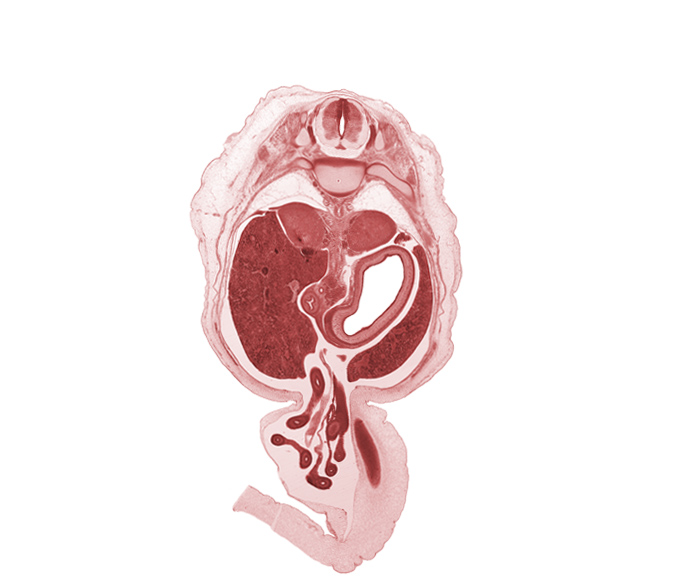

0 μm

Carnegie Embryo #462 | Location: 4-03-01

Keywords: T-10 / T-11 intervertebral disc, T-11 spinal ganglion, aorta, bile duct, centrum of T-11 vertebra, descending part of duodenum (second part), distal limb of herniated midgut, head of rib 11, jejunum, left lobe of liver, lumen of body of stomach, mesentery, notochord, proximal limb of herniated midgut, superior mesenteric artery, testis, umbilical vein

Source: The Virtual Human Embryo.